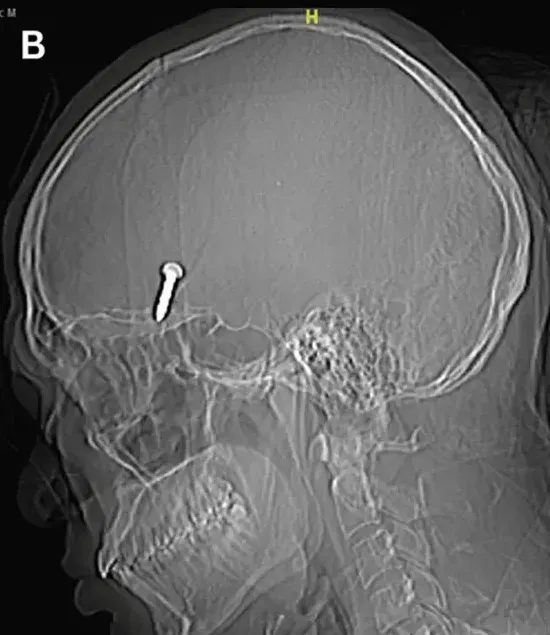

工安意外

機台

頭部

夾住

變黑

臉部

瘀青

發紺

創傷性腦損傷(TBI)處置原則

台南市消防局